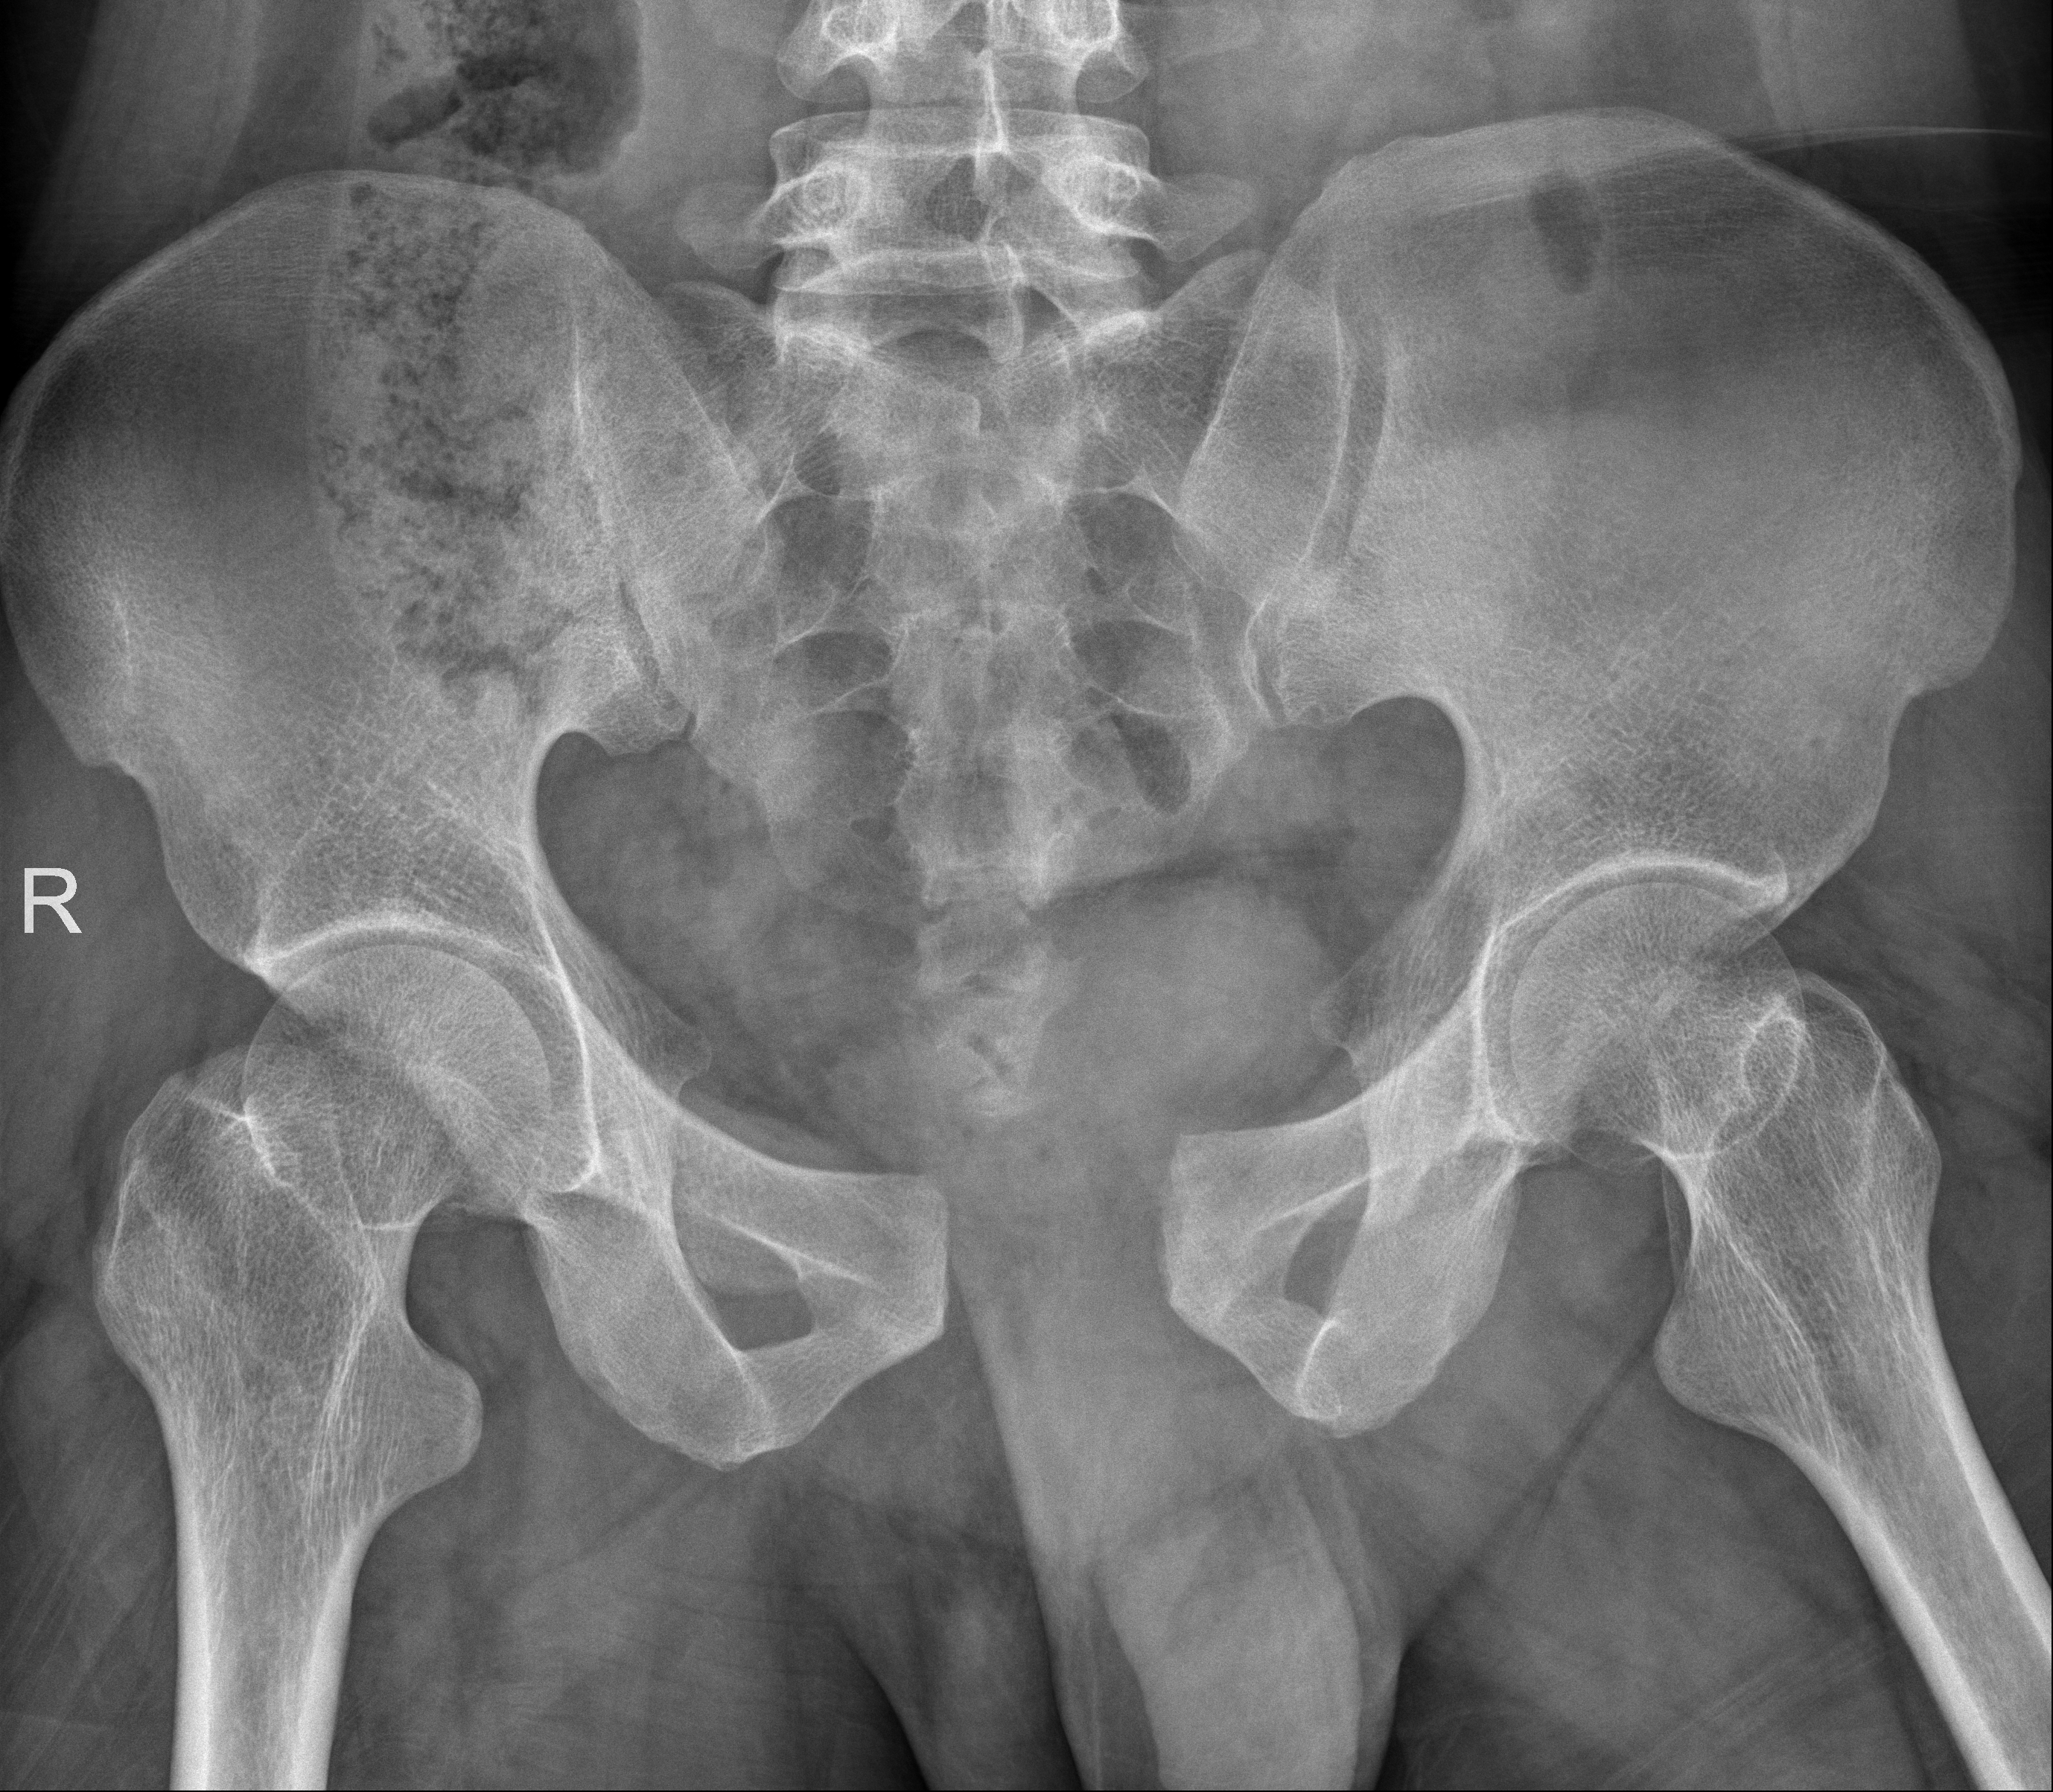

术前

6月12日晚北京遭遇大风天气,一名外来务工人员不幸从约六层楼高处坠落,生命垂危。潞河医院接到120急救电话,医疗部了解相关情况后迅速启动创伤救治绿色通道,确保患者得到及时救治。经过初步检查,患者被诊断为合并创伤性休克、骨盆粉碎性骨折、多发肋骨骨折、血气胸,并紧急收入重症监护室进行生命支持治疗。为提供最佳治疗方案,第二天上午医院迅速召集了多学科专家团队进行会诊。在医疗部指挥下,由骨中心主任刘亮、创伤骨科主任王雪飞牵头,专家们针对患者病情进行了全面细致的分析、评估和讨论,制定了详尽的手术计划。患者因骨盆粉碎性骨折导致失血性休克,创伤严重程度评分高达25分,属于严重多发创伤。在此情况下,对骨盆骨折进行快速有效的手术固定止血成为关键。得益于多学科团队的紧密合作和高效沟通,患者在下午被紧急送进手术室。在胸外科、麻醉科、重症监护室等多个科室的共同努力下,借助骨科机器人的精准操控,创伤救治团队迅速完成了对不稳定骨盆骨折的闭合复位和微创螺钉内固定手术。骨科机器人的应用显著缩短了手术时间,提高了手术效率。